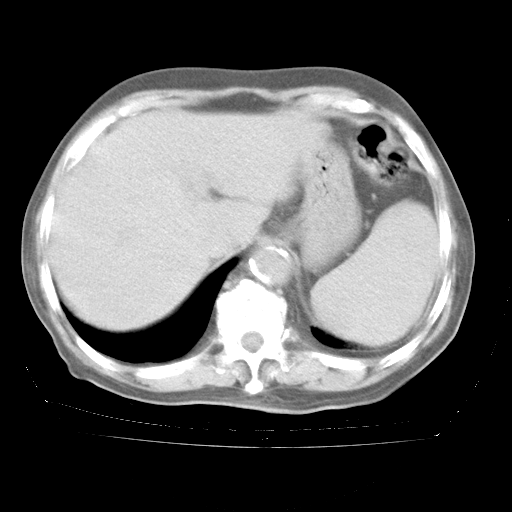

4月28日肺部CT——再次出现类似去年5月9日——透光度降低,“间质性”改变。

4月28日肺部CT——再次出现类似去年5月9日——磨玻璃样、间有“粟粒样”改变。

4月28日肺部CT

个人阅读4.14日肺部CT平扫:纵隔窗无异常,但肺窗示:双下肺内、后基底段有片絮状侵润影,部位以后基底段为著,以间质改变为主,呈急性肺泡炎征像,和首次住院影像学有相似之处。仅是个人读片,明日请相关专家再读片哈。其它建议同上。

今请临免主任会诊后认为:4月14日胸部CT已有双下肺间质性改变。患者病情复发多系激素减量过快不正规所致。目前甲强龙80mg/日,一周后酌情开始减量,不易过快。环磷酰胺若已停用,暂不使用。他同意目前抗菌药物使用,但应考虑是否加用B-内酰胺类抗菌药物(中性细胞明显增高);2、结核复发目前依据不足;3、若免疫全套各项指标正常,考虑多系特发性肺间质炎可能大。4、加强支持,并注意保护胃黏膜。